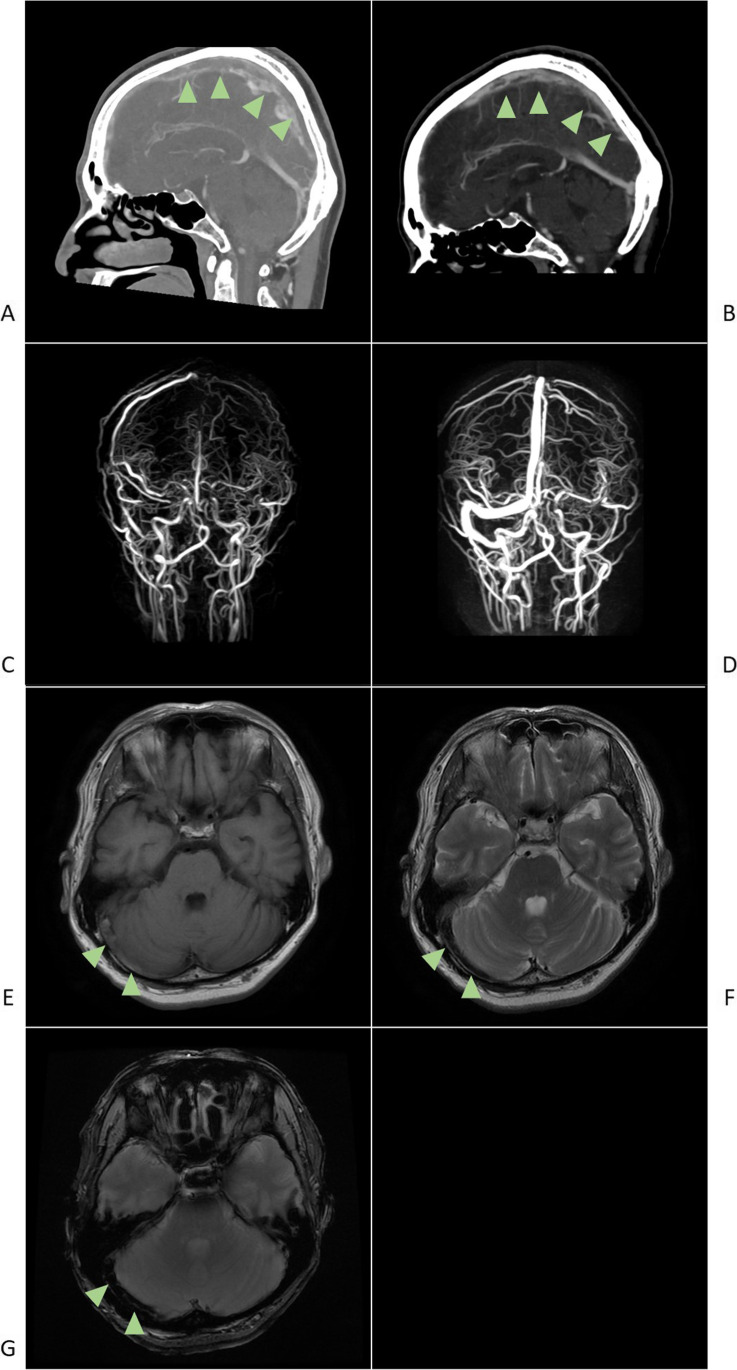

His headache was a combination of pulsative and tension types, predominantly felt around the bilateral occipital area. Nonetheless, it was mild; thus, he could still continue his office work, with over-the-counter pain reliever medication. No other common adverse events of vaccination were noted. On admission, he was alert and had no neurological deficit. His platelet count was normal (271,000/µL [reference range: 158,000–348,000]), but his D-dimer level was elevated (6.01 µg/mL [reference value: < 1.00]). Brain CT and MRI (Fig. 1), which were both conducted 7 days after second vaccination, showed thrombosis in the superior sagittal sinus, right transverse sinus, right sigmoid sinus, and right internal jugular vein [3]. There were no remarkable abnormalities in brain parenchyma. Nasopharyngeal swab samples were negative for severe acute respiratory syndrome coronavirus 2 (SARS-CoV-2) according to the polymerase chain reaction test. Blood tests for the risk factors of venous thrombosis such as antiphospholipid antibody and protein S/C showed no remarkable abnormality, and the screening test for antibodies against PF4–heparin was negative. After heparin treatment, his headache was relieved in 2 weeks, with sinus thrombosis partially disappearing.

Fig. 1.

a Sagittal view of the enhanced CT imaging of the brain showing CVST in superior sagittal sinus (arrow heads). b Sagittal view of the enhanced CT imaging of the brain showing partially disappearing CVST, 1 week after the admission (arrow heads). c MRV showing CVST in the superior sagittal sinus, right transverse sinus, right sigmoid sinus, and right internal jugular vein. d MRV showing partially disappearing CVST, 2 weeks after the admission. e MRI of the thrombosed right transverse sinus showing slight hyperintensity on the T1-weighted image (arrow heads). f MRI of the thrombosed right transverse sinus showing hypointensity on the T2-weighted image (arrow heads). g MRI of the right transverse sinus showing hypointensity on the T2*-weighted sequence (arrow heads). CT, computed tomography; CVST, cerebral venous sinus thrombosis; MRI, magnetic resonance imaging; MRV, magnetic resonance venography